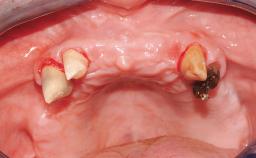

Immediate Loading of Four Implants in the Mandible and Final Restoration with a Full-Arch Metal Framework FDP

Pedro Tortamano, Luiz Otávio Alves Camargo

A fully edentulous 65-year-old woman was referred to our clinic for esthetic and functional dental rehabilitation. The patient presented with inadequate complete maxillary and mandibular prostheses, insufficient vertical dimension, and extensive tooth wear. The clinical examination and anamnesis showed no local or systemic contraindications, no signs or symptoms of bruxism, and an absence of smoking habits. The treatment proposed was implant placement in the mandibular interforaminal area and immediate loading with a fixed definitive prosthesis. A removable mucosa-supported complete prosthesis was indicated for the upper jaw, since its bone structure offered satisfactory retention and the financial condition of the patient disfavored a full-mouth implant-supported rehabilitation.

# of Implants 4

Type of Implants One-Piece

Defining Characteristics Fully edentulous lower jaw to be rehabilitated with two or more implants

Modality 3 or 4 interforaminal implants

Defining Characteristics Fully edentulous lower jaw to be rehabilitated with an implant-borne fixed dental prosthesis

Loading Protocol Immediate

Retention Screw-retained, with 4 or more splinted implants Screw-retained, with 4 or more splinted implants